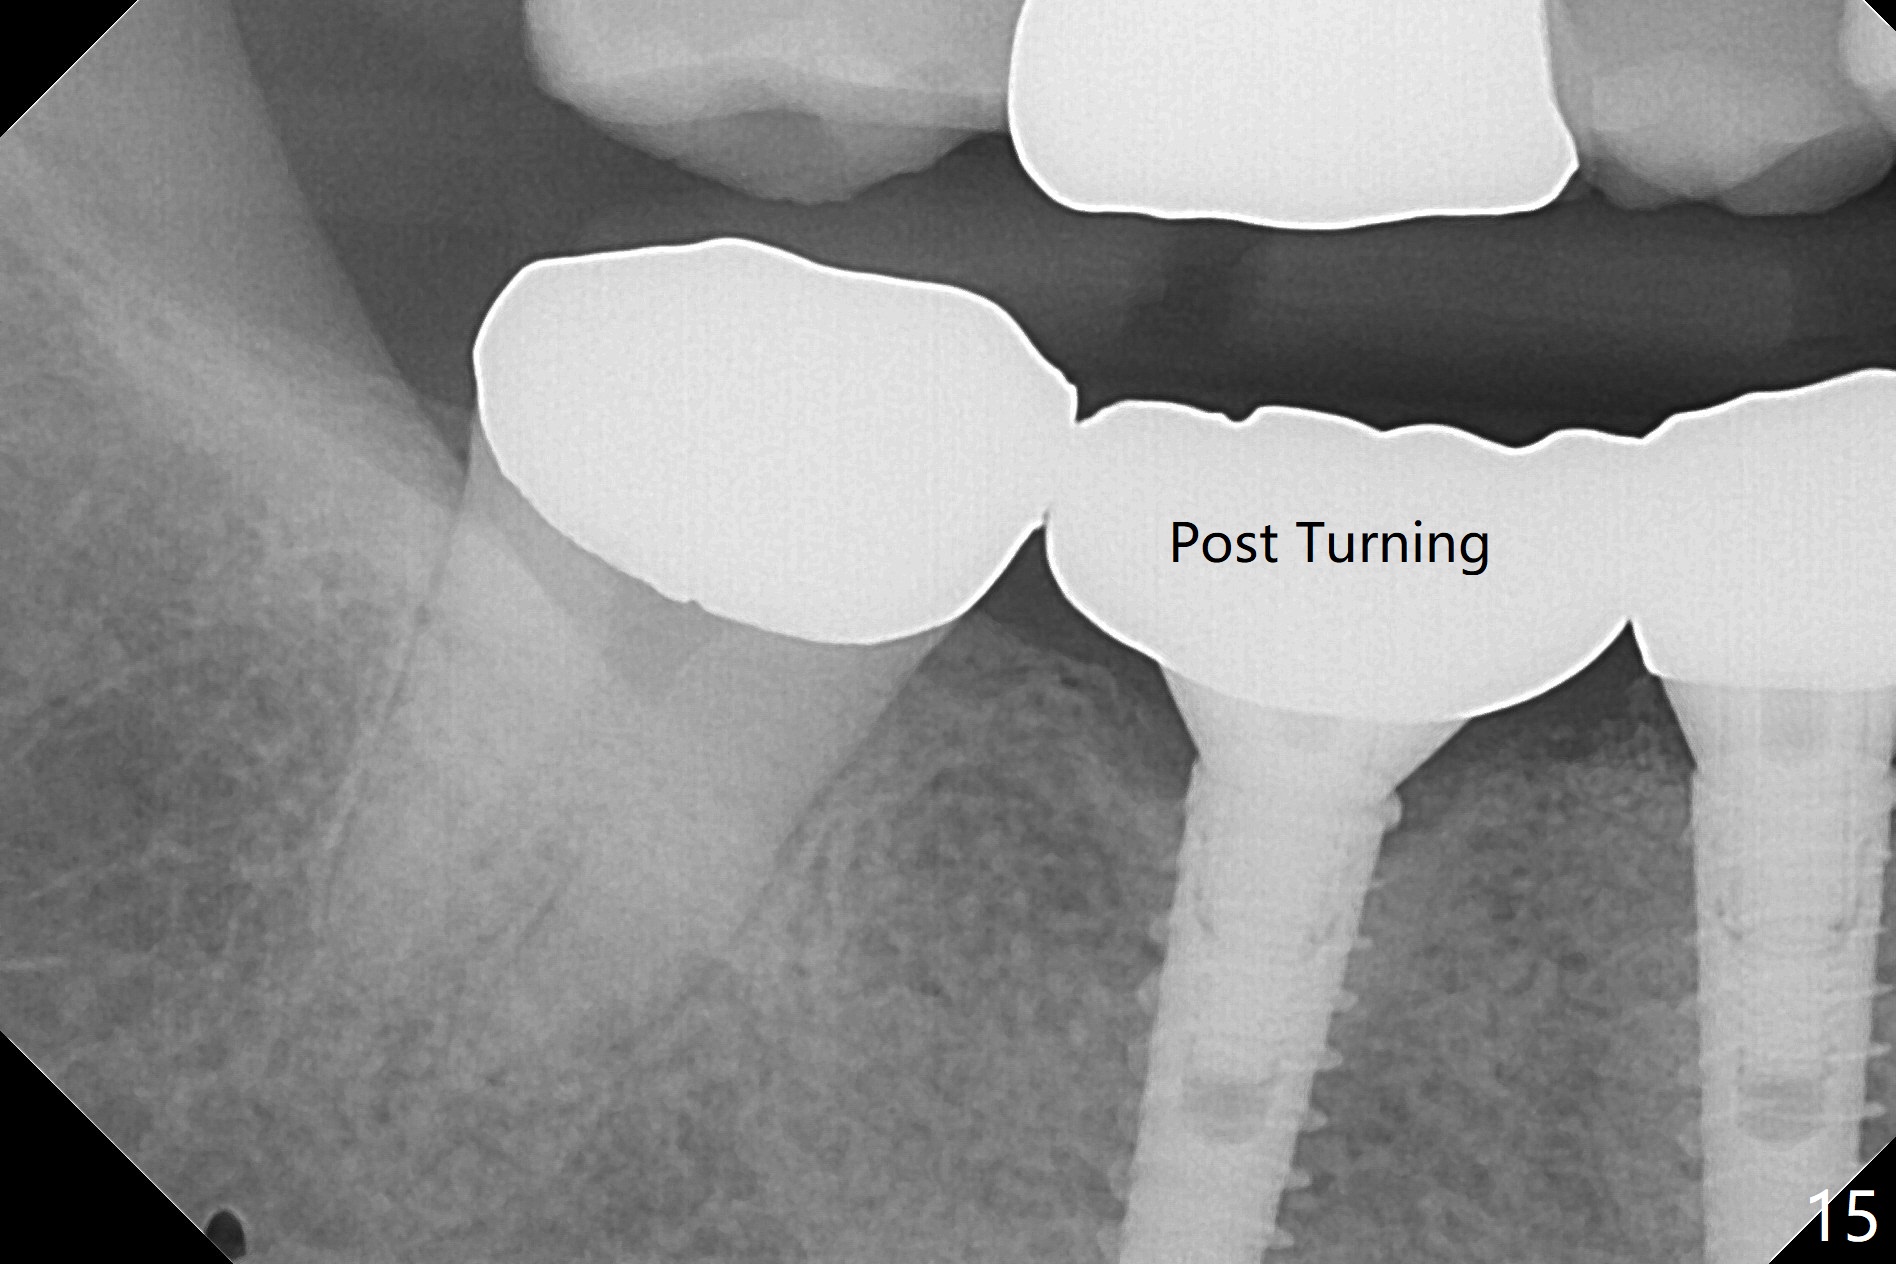

After incision, the ridge at #29 and 30 is found ~ 5 mm wide buccolingually. To place a 4x11 mm IBS implant at #30, the ridge is expanded using BEB technique (bone expansion and bending, Fig.1). It appears that the initial osteotomy at #29 is mesial (Fig.1 yellow dashed line: the distal surface of the root of the tooth #28). After moving the osteotomy distal, the final implant position at #29 (4x11 mm) is within normal limit (Fig.2). The bone at #29 seems to be not so dense that bending (using 1.6 mm drill) is not necessary (using Magic Split and Magic Expanders 3 and 3.8 mm). Later the implant at #30 (4x11 mm) is placed deeper (Fig.3). After placing bone graft around the implants/abutments and suturing, the ridge looks wider with apparent formation of the gingival bands around the abutments (Fig.4 *). Three months and a half postop, bone loss is minimal (Fig.5) and gingival bands forms around the abutments (Fig.6). Fig.7 is taken 1 month post cementation (panoramic X-ray). The patient chews normally 1 year (Fig.8) and nearly 2 years (Fig.9,10) post cementation. The crown at #31 needs recementation 2 years 7 months post #30 cementation; the incomplete seating of the abutment was noted for the first time (Fig.11). Five months later the patient is going to be retired and wants to travel abroad. After approval, the access hole was reopened; articulating paper shows under occlusion of the crown (Fig.12). Since the gap between the abutment and the implant is large, the abutment/crown complex seems to be necessary to be turned (Fig.13 curved arrow). The proximal surfaces of the crown need to be trimmed (straight lines). After turning, the crown sits down with screw tightening; the patient feels pain from the gingival cuff (Fig.14). After turning, the abutment appears to be completely seated (Fig.15). In fact the mesial and distal surfaces of the crown should have clearance from the neighboring teeth (Fig.14) so that pick-up impression is able to hold the crown/abutment complex securely (Fig.16: *). The crown is separated from the abutment after crown repair. They are seated together (loose connection) using the crown as a guide to seat the abutment. BW is taken without the crown. It appears that the abutment remains seated completely (Fig.17). The apical space is equal between #29 and 30 (Fig.17, as compared to Fig.5).